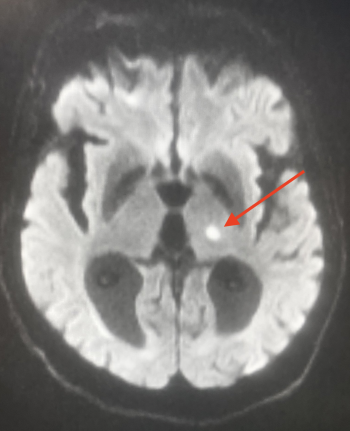

La RM sigue siendo el examen de referencia y puede revelar :

- Lagunas recientes: hiper en T2 y FLAIR.

- Fase aguda: mismas anomalías de difusión y de ADC que para otros tipos de ictus (hiper en difusión e hipo en ADC para un infarto).